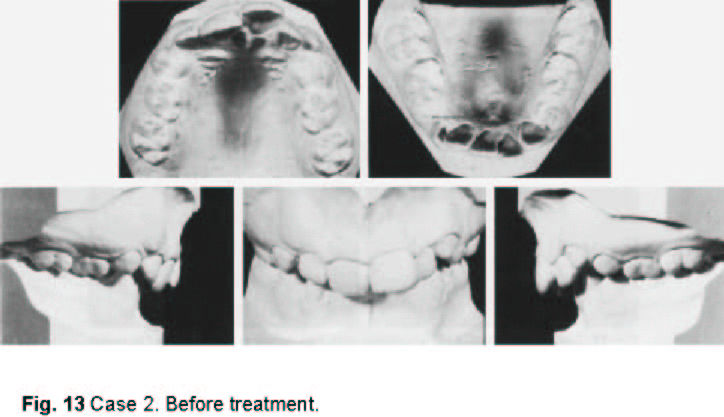

An 11-year-old female presented with a Class II, division 1 malocclusion and severe crowding of the upper and lower anterior segments. The maxillary right and mandibular left permanent canines were unerupted and completely blocked out. The patient had an 8mm overjet and 100% overbite, with the lower incisors occluding on the palate (Fig. 13).

Fig. 13 Case 2. Before treatment.